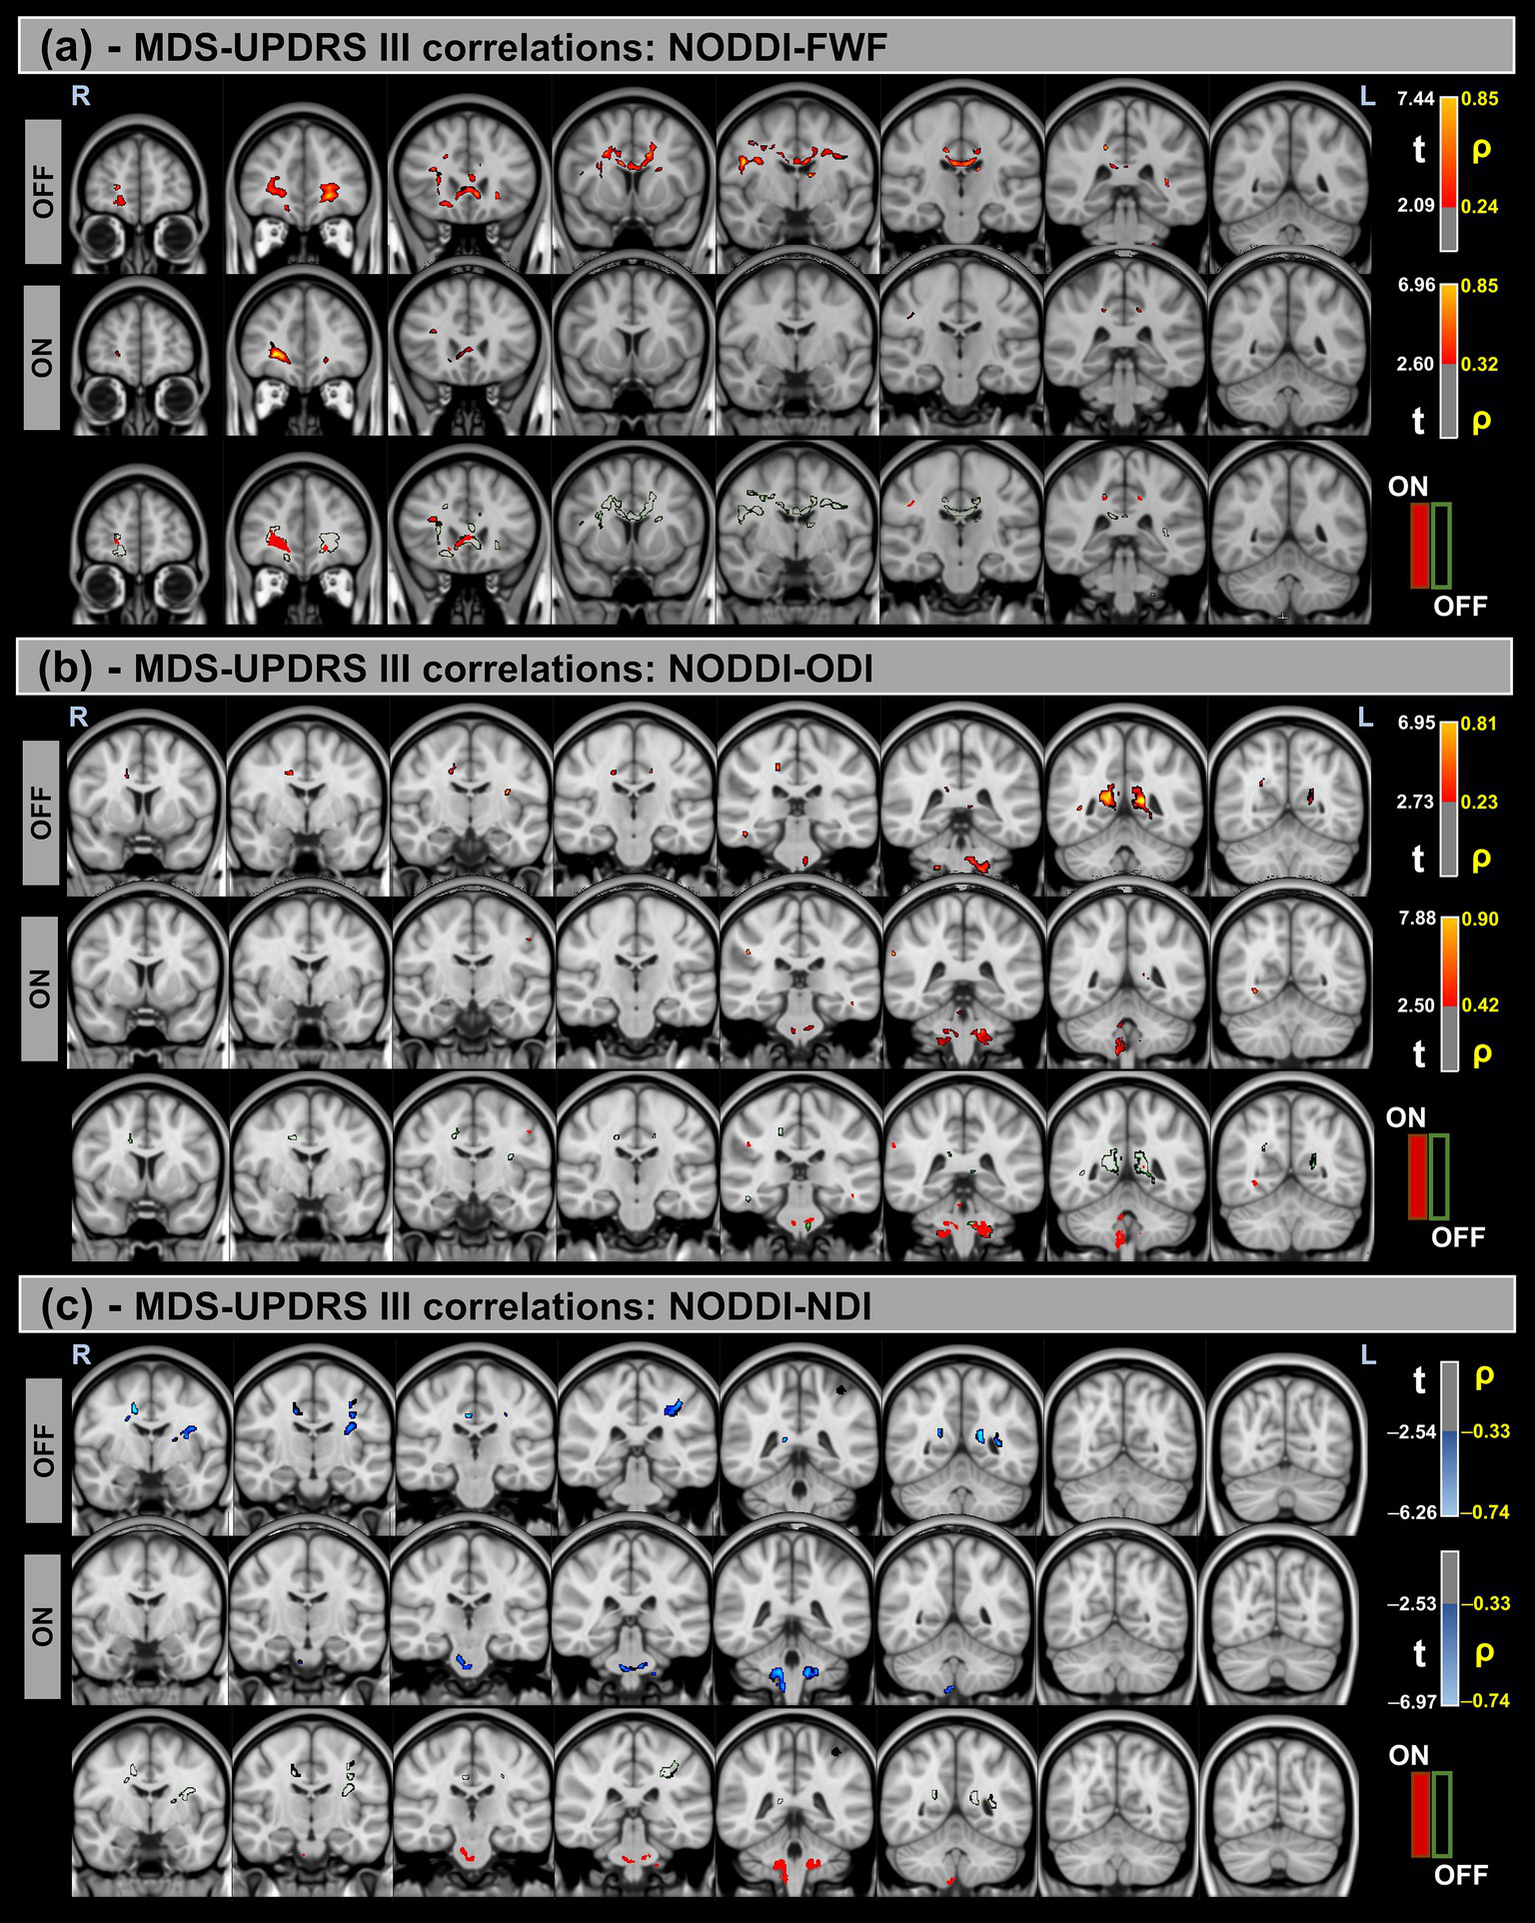

3.6 NODDI metrics and correlations with MDS-UPDRS III/H&Y scores

Figures 5, 6 show voxel-based correlations between NODDI metrics and MDS-UPDRS III/H&Y in the PD group across OFF and ON states.

Figure 5

Voxel-based correlations between NODDI metrics and MDS-UPDRS-III scores in the Parkinson’s Disease (PD) group. (a,b) Positive correlations with the FWF and ODI are shown warm colors (red-yellow). (c) Negative correlations with the NDI are shown cool colors (blue-light blue). The color bars represent t-values and corresponding correlation coefficients (ρ). Differences between OFF and ON states (green for OFF and red for ON) indicate a reduction in correlation strength during the ON state.

Figure 6

Voxel-based correlations between NODDI metrics and H&Y scores in the Parkinson’s Disease (PD) group. (a,b) Positive correlations with the FWF and ODI are shown warm colors (red-yellow). (c) Negative correlations with the NDI are shown cool colors (blue-light blue). The color bars represent t-values and corresponding correlation coefficients (ρ). Differences between OFF and ON states (green for OFF and red for ON) indicate a reduction in correlation strength during the ON state.

Significant positive correlations were observed between MDS-UPDRS-III and both FWF and ODI metrics, whereas significant negative correlations were found for the NDI. Additionally, differences in correlation patterns were detected between the OFF and ON states.

Similar trends were observed for the H&Y scores, with significant correlations in the same direction of MDS-UPDRS-III for all NODDI metrics.

Table 7 provides a summary of these findings, including cluster volumes, t-values, ρ-values, and the percentage change in volume between the OFF and ON states.